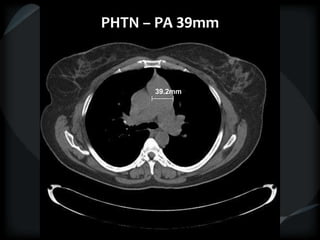

PHTN – PA 39mm

39.2mm

PHTN and septal thickening

? PVOD